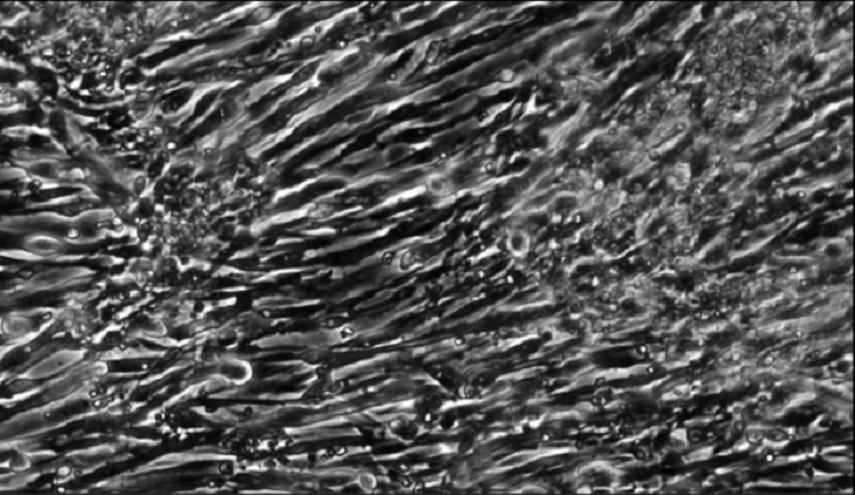

زراعة عضلات من خلايا جلدية لأول مرة في العالم

علوم وتكنواوجيا _الكوثر: تمكن العلماء من إنماء عضلات فعالة باستخدام الخلايا الجذعية التي تم إنشاؤها من الجلد.

الثلاثاء 9 يناير 2018 - 20:39 بتوقيت مكة